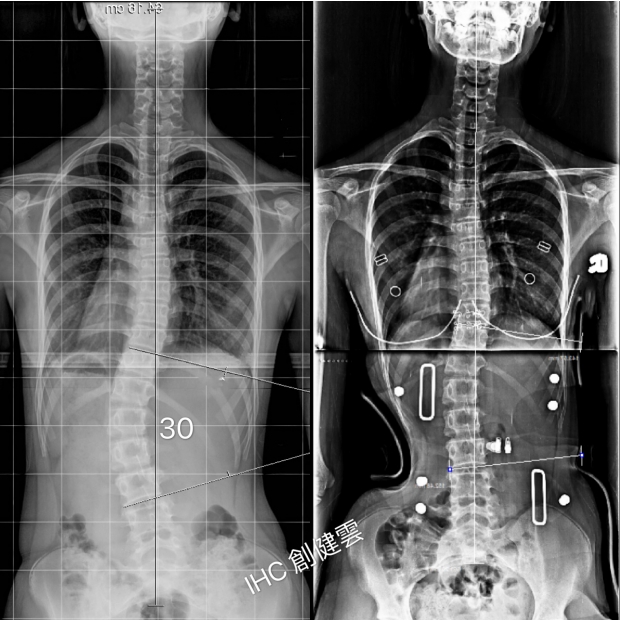

15歲中度脊椎側彎女孩

腰彎30度